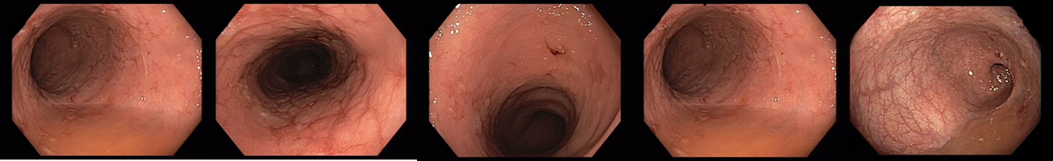

2017/10 zahájena léčba vedolizumabem

Promptní klinická remise

018/2 Slizniční zhojení. Monoterapie vedolizumabem

2021/10 změna na s.c. podávání

2022/9 klinická, laboratorní i endoskopická remise

Slizniční zhojení